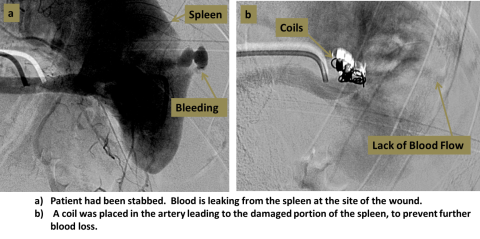

An interventional radiologist accesses the femoral artery at the groin. Small catheters and wires are used to navigate into the chosen artery, confirmed with angiography. An occluding substance can then be injected, or small coils can be placed into the artery to block the vessel.

Two step diagram of embolization process. A. Showing a spleen and bleeding. B. Showing the placing of a coil in the artery leading to the damaged portion of the spleen, to prevent further blood loss.